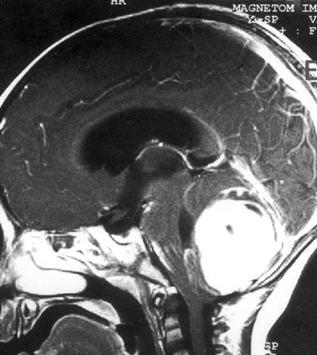

问题 病历摘要:??患儿男性,11岁。半年前开始出现行走不稳,常无故跌倒。半月前出现发作性剧烈头痛,伴恶心呕吐。体检:T36℃,P100次/分,R22次/分,BP100/60mmHg,神清,言语较缓慢,双眼外展约不及边,双眼侧视时有小幅度水平眼震。四肢肌力正常,右上肢肌张力较低,坐位姿势不稳,常不自主摇晃,双上肢指鼻不准,行走蹒跚步态,足距扩大,身前倾。 患儿目前出现了哪些方面的临床症状